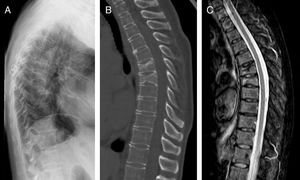

ResultadosLas características de las pacientes se muestran en la tabla 1. La edad media al inicio del tratamiento fue de 66±7,7 años. Cuatro pacientes tenían historia previa de fracturas por fragilidad y solo una tenía factores de riesgo de OP secundaria (inhibidores de la aromatasa, caso 7). Nueve pacientes (90%) habían recibido otros tratamientos previos al inicio de DMab (7 bisfosfonatos orales, 5 ranelato de estroncio, 2 raloxifeno, 1 tibolona y 1 calcitonina). Las pacientes recibieron entre 3 y 9 dosis de DMab, siguiendo la posología recomendada en ficha técnica, con una media de 6±1,7. El motivo de retirada del fármaco fue manipulación dental (casos 1 y 6), bajo riesgo de fractura (caso 5) y cumplimiento del tiempo estimado por el médico prescriptor. En todos los casos salvo en dos se había realizado una densitometría ósea previa al inicio de DMab. La media de T-score antes del tratamiento fue -2,6±0,6 en cuello femoral (CF) y -3,0±1,3 en columna lumbar (CL). Asimismo, en todos los casos salvo en dos (casos 7 y 9) se realizó densitometría transcurridos al menos 6 meses tras la retirada del tratamiento, con una media de T-score -3,2±0,7 en CF y -3,2±1,6 en CL. Los marcadores de recambio óseo tras al menos 10 meses de la suspensión se objetivaron elevados con una media de telopéptico del colágeno (CTX) de 1,32±0,32 ng/ml y de propéptido del colágeno (P1NP) de 181,6±104,1 ng/ml. El tiempo transcurrido entre la última dosis del fármaco y la aparición de la primera fractura varió entre 8 y 18 meses, con una media de 10,9±3,3 meses. Las pacientes presentaron entre 2 y 9 fracturas, registrándose un total de 49 fracturas. En la figura 1 se muestran las pruebas de imagen diagnósticas del caso 10. En todos los casos ocurrieron de forma espontánea, sin traumatismo asociado. Las vértebras más afectadas fueron L3, L5, D6, D7, D9 y D11. A dos pacientes (casos 1 y 2) se les realizó vertebroplastia, produciéndose en ambas nuevas fracturas vertebrales. En una paciente (caso 9) se inició alendronato seis meses después de suspender DMab siguiendo las recomendaciones de la European Calcified Tissue Society (ECTS) y pese a ello presentó fracturas vertebrales (fig. 2). Con respecto al tratamiento farmacológico recibido tras las fracturas, las opciones más utilizadas fueron teriparatida (30%), bisfosfonatos orales (20%) y DMab (20%).

En nuestra serie una paciente recibió alendronato 6 meses después de la suspensión de DMab siguiendo las recomendaciones de la ECTS, y presentó 9 nuevas fracturas tras esta medida. La ETCS recomienda en caso de suspensión del tratamiento con DMab comenzar tratamiento con otro fármaco antiosteoporótico: administrar una dosis única de ácido zoledrónico o un bisfosfonato oral durante al menos un año10. Antes de la publicación de estas recomendaciones, era frecuente que los pacientes que discontinuaban DMab no recibieran tratamiento alternativo para la OP, sobre todo si se había alcanzado el nivel de osteopenia y no se habían producido nuevas fracturas. En nuestra serie el clínico responsable del paciente consideró en 7 casos (7/10, 70%) que se había realizado un adecuado periodo de tratamiento con DMab. Con los posteriores conocimientos adquiridos de eficacia y seguridad del tratamiento con DMab y con los datos del estudio de extensión del FREEDOM11,12, una actual revisión del riesgo de fractura de los pacientes que suspendieron el tratamiento quizás nos hubiera inclinado a prolongar el tratamiento con DMab y no podemos descartar que el riesgo de fractura fuese todavía alto en algunas de nuestras pacientes a las que se retiró el tratamiento. Es relevante que dos de las pacientes suspendieron el tratamiento para hacerse una manipulación dental, lo que centra el problema en la necesidad de adecuadas guías de suspensión de la terapia antirresortiva compartidas con los estomatólogos. Según las últimas recomendaciones SER de osteoporosis en pacientes tratados con antirresortivos a los que se vaya a realizar un procedimiento dental no se recomienda suspender el tratamiento con bisfosfonatos ni con DMab. Si existen factores de riesgo de osteonecrosis de los maxilares y el procedimiento quirúrgico va a ser extenso se contempla la posibilidad de suspensión solo en el caso de los bisfosfonatos13.